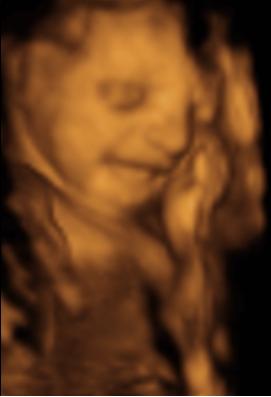

A második képen nyitva van a szeme is